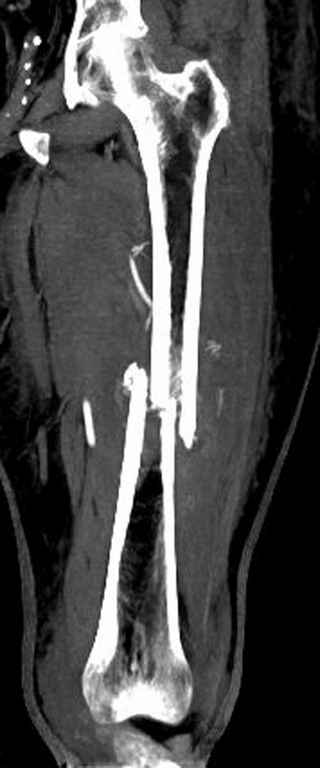

Здесь случай 66 летней пациентки со спонтанными болями в левой нижней конечности, обратилась в приемное, сделаны снимки бедра и КТ.

Патологический перелом бедра, конечность на вытяжении.

Со слов, больная ничем не болела, только последние 3 месяцев чувствовала боли в бедренной области. КТ брюшной полости подтвердил увеличенную правую почку. (5-6)

С минимальным рассверливанием и ретроградным методом провели остеосинтез бедра 12 мм гвоздем. (17-20)